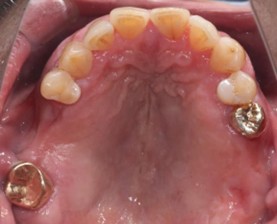

70代 女性

治療前

治療後- リスク・副作用

- 術後疼痛、歯肉腫脹

- 治療の費用

- 合計¥1,126,000(税込)

【内訳】

インプラント(2本)¥880,000

その他費用¥246,000

(薬・注射・レントゲン・ソケットリフト骨造成・サージカルステント・CT・データ分析) - 年齢/性別

- 70代/女性

- 患者の具体的な症状

- 右上56欠損のため義歯を使用していたが不安定で十分噛めないため、インプラント治療を希望

- 検査方法

- コーンビームCT、レントゲン撮影

- 診断結果

- 右上56欠損

- 治療詳細

- 右上56部、コーンビームCTによる画像診断で垂直的な骨高、骨密度の不足のため、ソケットリフトによる骨再生治療とインプラント埋入2本を同時にショートインプラントを用いて行った。

- 通院回数

- 7回

- 治療期間

- 7か月